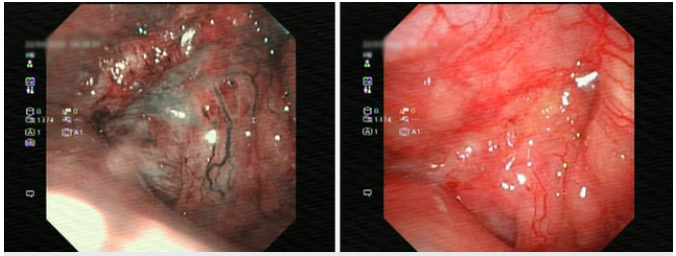

Nội soi phát hiện khối u ở ṿm họng. Ảnh: BVCC